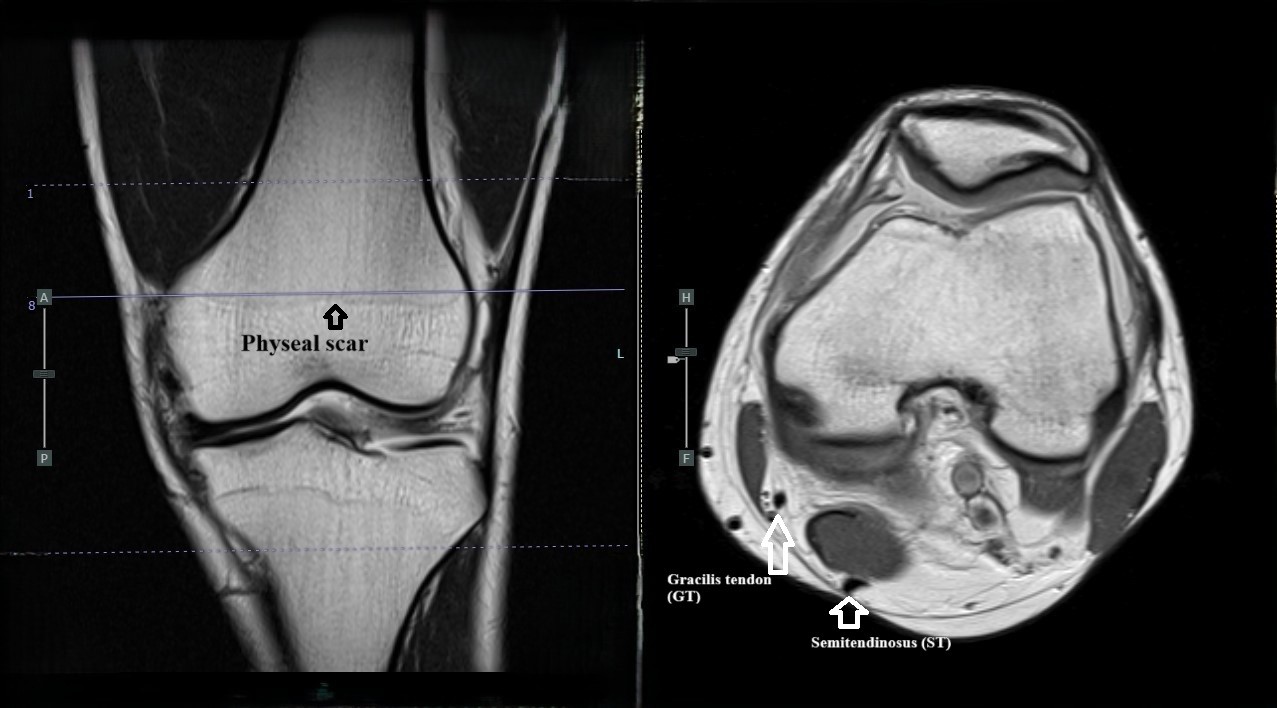

Methods: A retrospective cohort study was conducted in 210 patients (169 men, 41 women) who underwent single-bundle ACLR with quadrupled hamstring autografts at Maharat Nakhon Ratchasima Hospital between 2017 and 2023. Anthropometric data were collected; preoperative MRI measurements of the semitendinosus and gracilis tendons were performed. Graft diameters were recorded intraoperatively following the MRI assessment. All measurements were performed by a single observer. Logistic regression was used to identify predictive factors; a receiver operating characteristic curve was used to evaluate the diagnostic accuracy of the model.

Results: Among the 210 patients, 51 (24.3%) had graft diameters < 8 mm. Those with grafts ≥ 8 mm were predominantly men and had greater height, weight, and MRI-derived tendon dimensions. Multivariate analysis identified the semitendinosus tendon cross-sectional area (CSA-ST) as the sole independent predictor. A CSA-ST ≥ 13.4 mm² predicted graft diameters ≥ 8 mm with 70.4% sensitivity (95% CI, 62.7–77.4%), 80.4% specificity (95% CI, 66.9–90.2%), a positive predictive value of 91.8% (95% CI, 85.4–96.0%), a positive likelihood ratio of 3.6 (95% CI, 2.1–6.3), and an area under the receiver operating characteristic curve of 0.79 (95% CI, 0.69–0.82).

Conclusions: The CSA ST measured on preoperative MRI is a reliable predictor of hamstring graft adequacy in ACLR. A threshold of 13.4 mm² can assist in surgical planning and graft selection, particularly in patients with smaller body sizes. These findings underscore the importance of incorporating MRI-based assessments into routine preoperative evaluations.